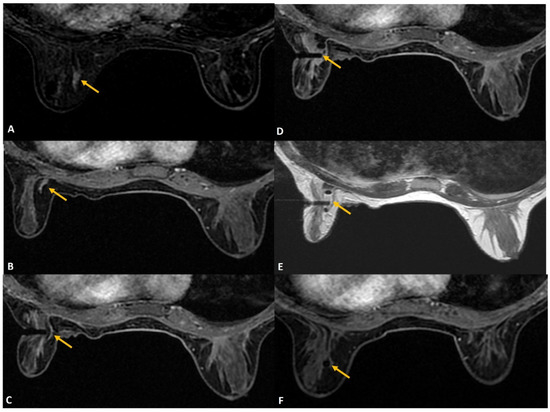

Figure 1.

A 36-year lactating mother diagnosed with left breast inflammatory breast cancer underwent staging MRI. (A). Sagittal post contrast T1w fat-saturated image showed a segmental non-mass enhancement (yellow arrows) in the upper outer quadrant of the right breast. This was also distinctly FDG avid on PET scan (not shown here). (B). Axial staging scan showed diffusely enhancing mass in the left breast correlating with known cancer (red asterisks). Segmental non-mass enhancement was also seen in upper outer quadrant of the right breast (yellow arrow). (C). MRI-guided biopsy shows the tip of the obturator in correct location with surrounding post-biopsy hematoma (yellow arrow). Histology was reported as fibrocystic change.